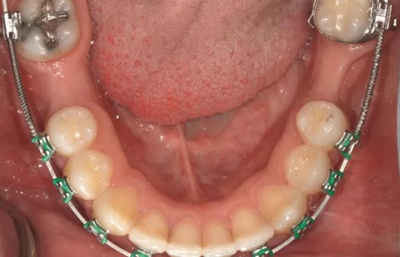

圖1b.臨床檢查顯示牙槽嵴萎縮,右下第一磨牙的無牙間隙近遠中距離為6.5mm,左下第一磨牙為9mm

為患者采用了直絲弓自鎖托槽(Damon,Ormco)。最開始用0.016×0.025 英寸的不銹鋼弓絲(Damon,Ormco)進行矯正和排齊,歷時7 個月。在磨牙直立加力之前,下頜第一磨牙位點無牙區(qū)的近遠中距離為右側(cè)6.5mm、左側(cè)9mm(圖1)。磨牙遠移和直立的目標是實現(xiàn)雙側(cè)最終冠修復體的近遠中直徑達到10mm。右側(cè)第一磨牙位點的大小差異比左側(cè)更大,牙槽嵴吸收更多,頰舌徑約4.5mm(圖2)。在詳細解釋同期牙槽嵴增量和加速磨牙直立程序后,患者選擇右側(cè)位點進行種植治療。因此,為了加速該位點的空間建立,圍繞第二磨牙行選擇性去皮質(zhì)術(shù)和同期牙槽嵴增量術(shù)。